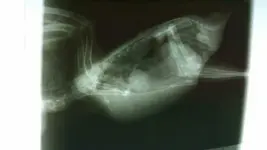

It's because she already has a egg inside her that we need her to push out. Look at the right side of her xray and you can see the egg, she just needs to push it out, it's taking all her calcium. I'm just following the avian vets instructions

• uploadfromtaptalk1445194401745.webp

uploadfromtaptalk1445194401745.webp

20.8 KB · Views: 131

We are too remove it as soon as she is done